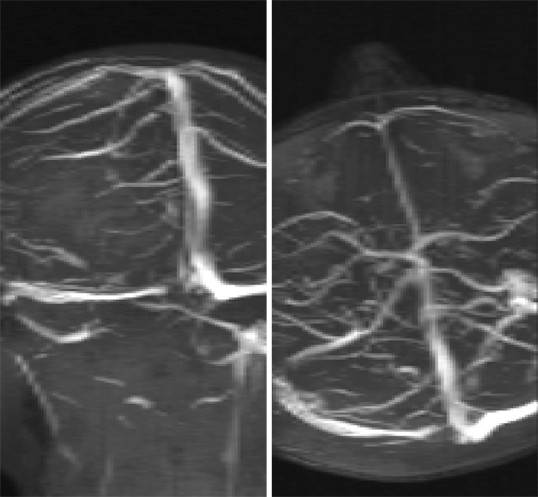

Abbildungen und Graphiken: Die zerebrale ...

Abbildungen und Graphiken: Die zerebrale ... from www.kup.at